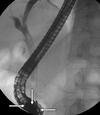

3

Q

A

common bile duct